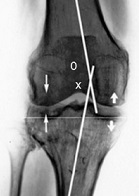

Diagnostic. O consolidare defectuoasa a tibiei proximale se defineste prin orice modificare a axului mecanic al membrului inferior, localizat la nivelul tibiei proximale. Evaluarea radiologica adecvata (intreg membrul inferior cu incarcare in incidente antero-posterioara, laterala si oblica) a membrului implicat si contralateral reprezinta fundamentul pentru planning-ul preoperator al unei osteotomii de corectie. Evaluarea deplasarii si angularea in toate planurile este importanta pentru determinarea tipului si detaliilor tehnice de corectie. Scurtarea si malrotatia membrului inferior sunt cel mai bine cuantificate clinic. Scanarea CT poate furniza documentari suplimentare si serveste planning-ului de corectie al deformarii. Un rol suplimentar al CT-ului poate fi evaluarea unei deplasari articulare; cu toate acestea, consideram ca aceasta poate fi lamurita cu ajutorul unor radiografii oblice de buna calitate.

Detalii tehnice ale osteotomiei de tibie proximala. Inca o data, trebuie acordata o atentie deosebita planning-ului preoperator, incluzand aici si documentarea anvergurii miscarilor, stabilitatii ligamentare, deformarilor angulare, si functionalitatii articulatiilor soldului si subtalare asociate. Evaluarea radiografica, asa cum am mentionat anterior, trebuie sa includa intreg membrul inferior (sold-genunchi-glezna), cu incarcare, in incidenta anteroposterioara pentru a determina axurile tibiofemurale, anatomice si mecanice. Axul tibiofemural este format de intersectarea liniilor trasate prin axul lung al femurului si al tibiei. Un aliniament tibiofemural normal este de 5-7 grade in valgus. O linie dreapta din centrul capului femural spre centrul gleznei reprezinta axul mecanic. Un ax mecanic normal trece prin genunchi, medial de centrul rotulei, pe o radiografie antero-posterioara corect executata. Desi chirurgii zilelor noastre beneficiaza de sisteme de planning computerizate anterior osteotomiei, inca nu exista un consens pentru aliniamentul post-operator ideal pentru majoritatea patologiilor care afecteaza genunchiul. Pentru a preveni artrita compartimentelor medial sau lateral, favorizam corectarea axului mecanic 11 grade in varus sau 2-5 grade in valgus, in functie de varsta pacientului. Distructii articulare unicompartimentale severe sau laxitatea ligamentara pot influenta aceste determinari. In experienta noastra, supra-corectarea, in contrast cu sub-corectarea, este rareori responsabila de esec.